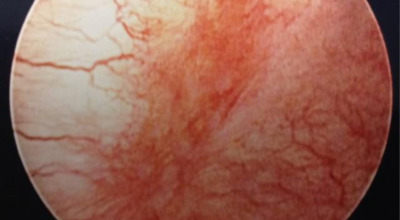

방광염 증상 - 혈뇨

소변을 볼때 화끈거림이 있다면서 피가 섞여 나오기도 합니다. 소아 방광염 증상의 경우 배의 통증, 38C 이상의 고온, 약점 및 과민 반응, 식욕 감소 또는 토악질와 같은 증상이 나타날 수 있어요.